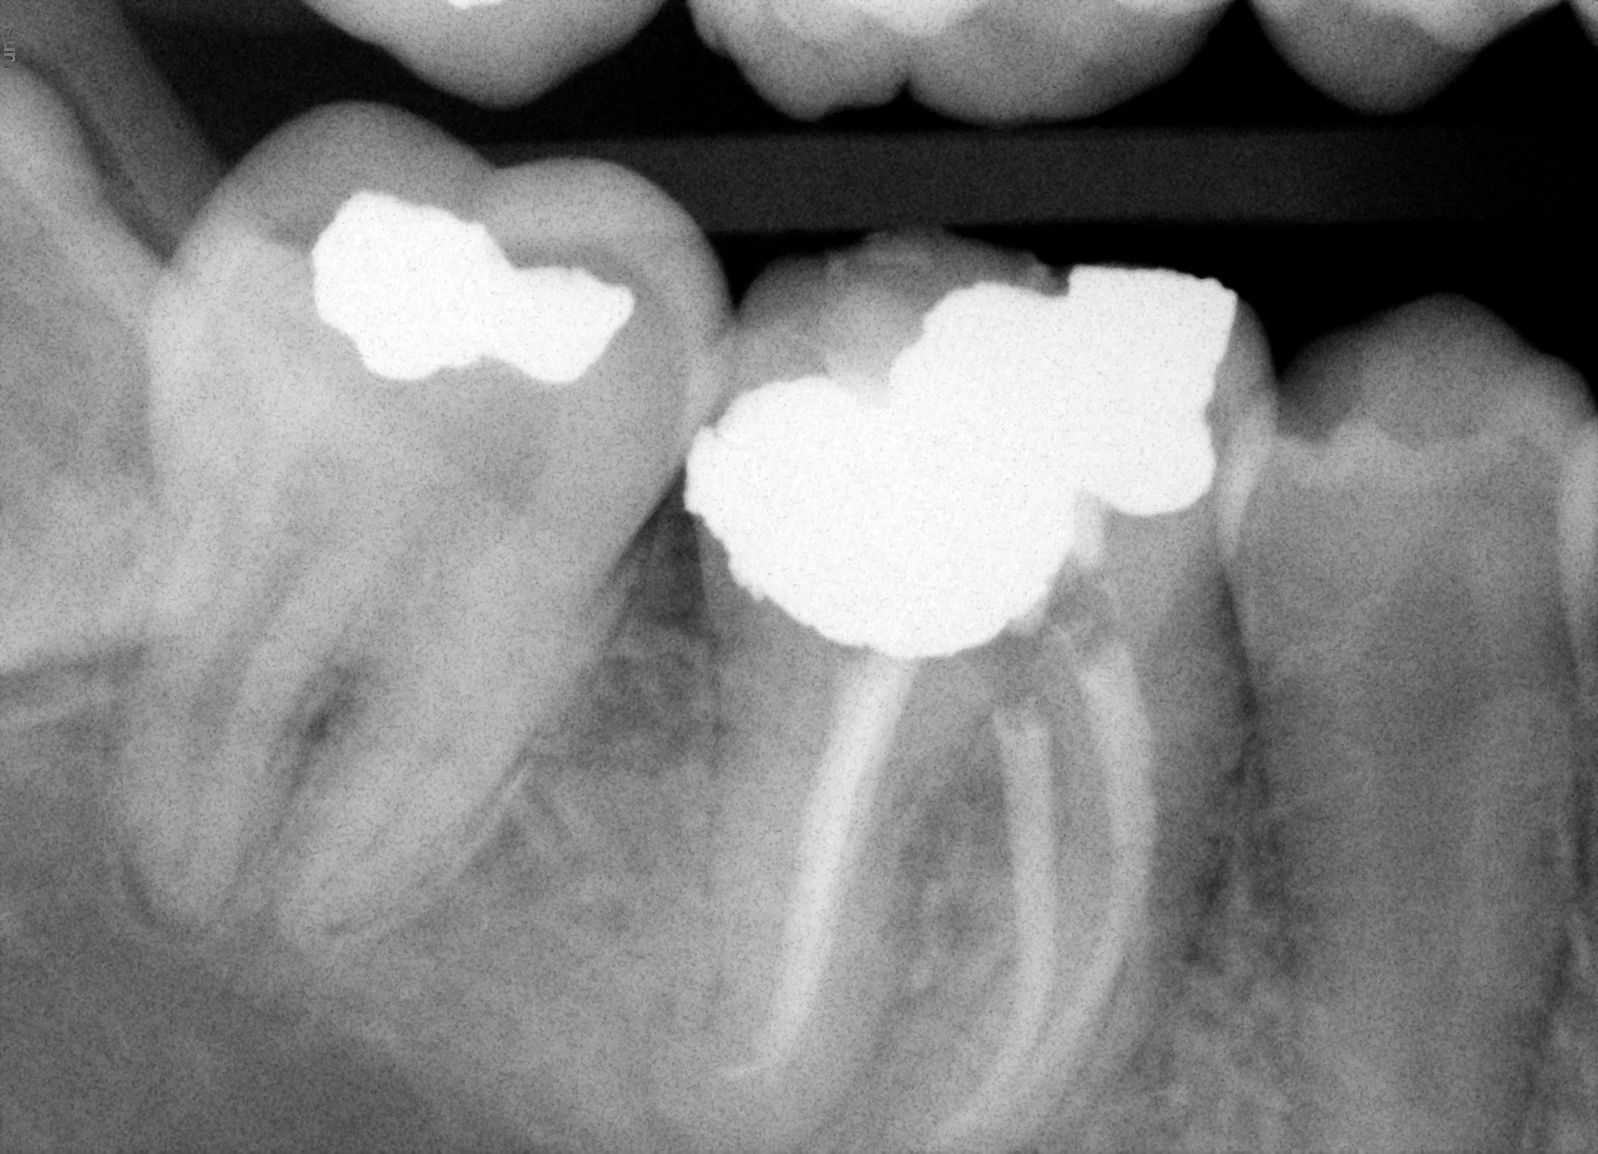

Ošetření zubů s 5 kořenovými kanálky

Dolní molár 46 s 5k.k. po ošetření. Vizualizace pomocí operačního mikroskopu umožňuje plnou kontrolu nad preparací i plněním kořenových kanálků.